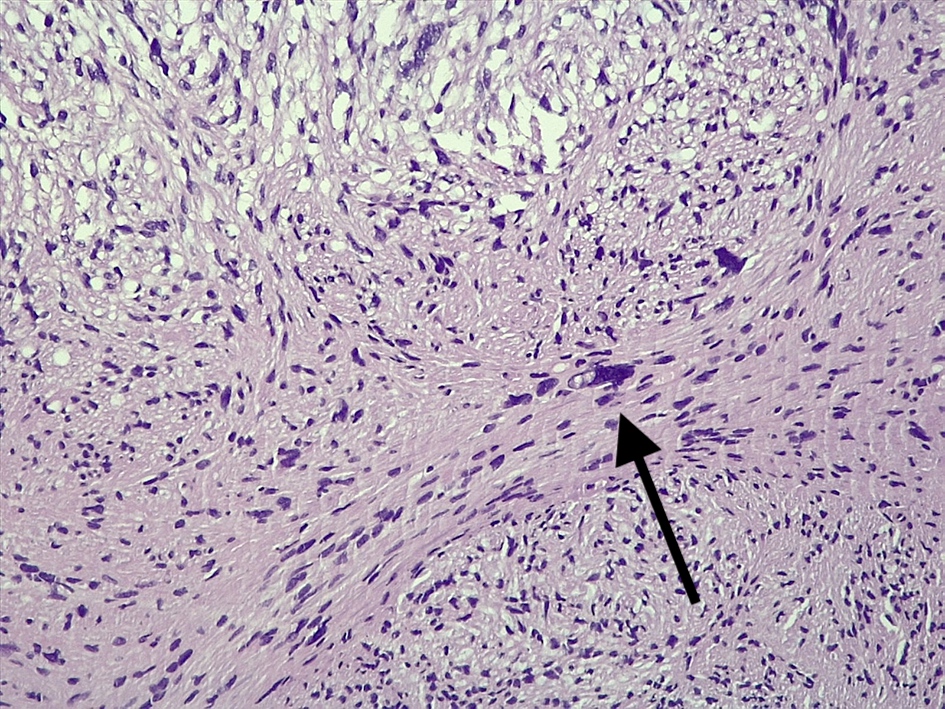

Microscopic (histologic) description

- Spindle cell tumor (usually biphasic) and composed of compact hypercellular areas (Antoni A tissue) showing nuclear palisading (Verocay bodies) and loose microcystic areas (Antoni B tissue) with collection of lipid laden histiocytes and thick walled hyalinized blood vessels (Surg Neurol Int 2020;11:454)

- Mitoses or focal degenerative atypia may be present

- Ancient subtype: characterized by scattered atypical or bizarre nuclei

Microscopic (histologic) images